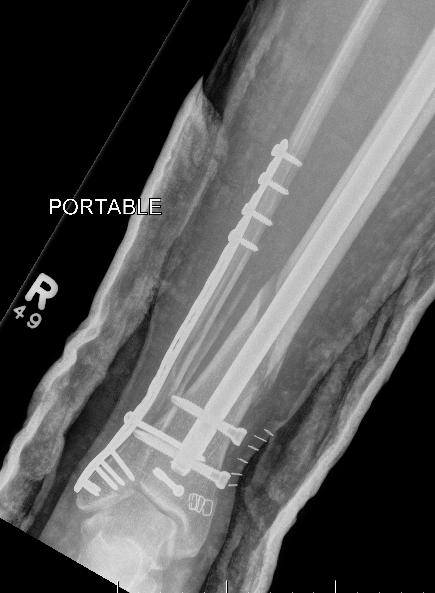

B. Distal Tibial ORIF with plate

Indications

- too distal to nail

- very comminuted / unstable

- intra-articular extension

Technique

1. Consider fixing the fibula

- will aid reduction / avoid malunion

- help control very unstable fractures

2. Anatomically contoured plates

- options of medial plate v anterolateral plate

- medial plate for varus deformity

- anterolateral plate for valgus deformity